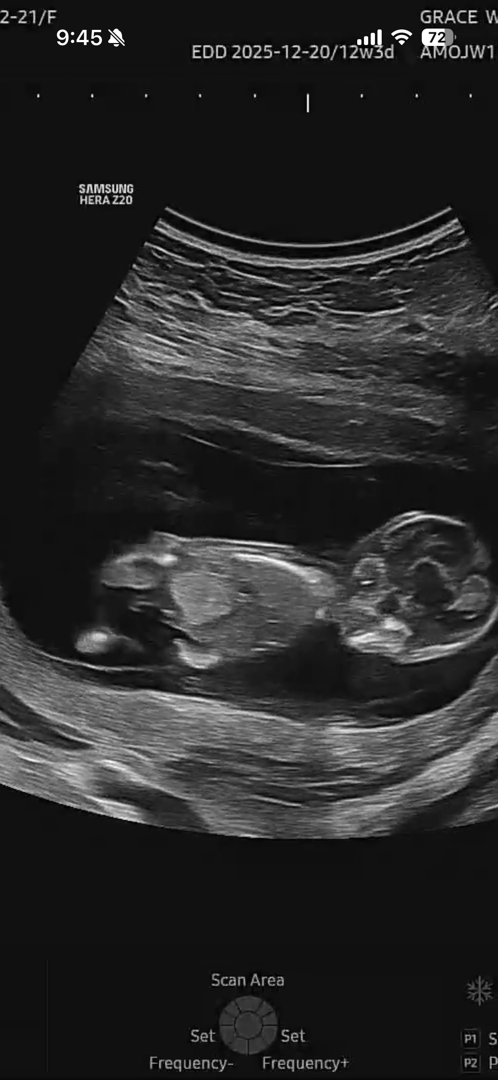

12주차맘입니당 아기성별뭐일까요 ㅎㅎㅎ

봐주세여ㅠㅠ

살짝 애매한데 딸 각도 같습니다